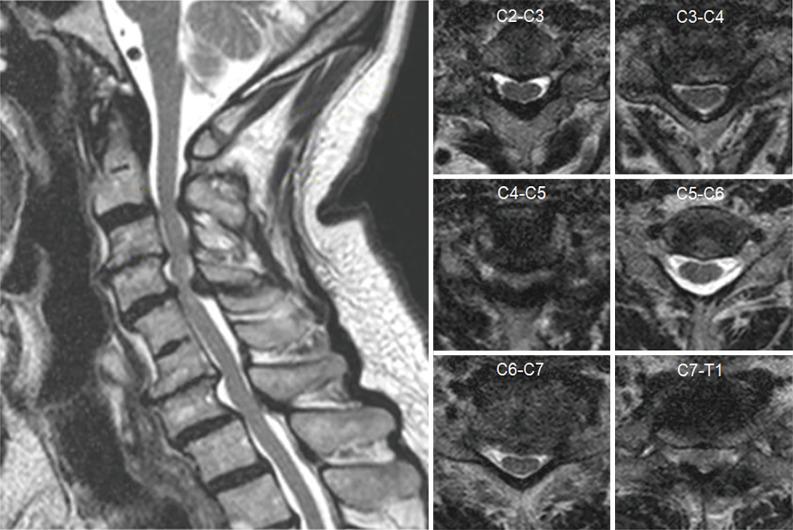

颈椎手术的术中影像引导

Intraoperative image guidance for cervical spine surgery.

Intraoperative image-guidance in spinal surgery has been influenced by various technological developments in imaging science since the early 1990s. The technology has evolved from simple fluoroscopic-based guidance to state-of-art intraoperative computed tomography (iCT)-based navigation systems. Although the intraoperative navigation is more commonly used in thoracolumbar spine surgery, this newer imaging platform has rapidly gained popularity in cervical approaches. The purpose of this manuscript is to address the applications of advanced image-guidance in cervical spine surgery and to describe the use of intraoperative neuro-navigation in surgical planning and execution. In this review, we aim to cover the following surgical techniques: anterior cervical approaches, atlanto-axial fixation, subaxial instrumentation, percutaneous interfacet cage implantation as well as minimally invasive posterior cervical foraminotomy (PCF) and unilateral laminotomy for bilateral decompression. The currently available data suggested that the use of 3D navigation significantly reduces the screw malposition, operative time, mean blood loss, radiation exposure, and complication rates in comparison to the conventional fluoroscopic-guidance. With the advancements in technology and surgical techniques, 3D navigation has potential to replace conventional fluoroscopy completely.

摘要

自20世纪90年代初以来,脊柱手术中的术中影像引导受到了影像科学各种技术发展的影响。该技术已从基于简单荧光透视的引导发展到基于术中计算机断层扫描(iCT)的先进导航系统。尽管术中导航在胸腰椎脊柱手术中更常用,但这种更新的成像平台在颈椎手术中迅速受到欢迎。本手稿的目的是探讨先进影像引导在颈椎手术中的应用,并描述术中神经导航在手术规划和实施中的使用。在本综述中,我们旨在涵盖以下手术技术:颈椎前路手术、寰枢椎固定、下颈椎内固定、经皮椎间融合器植入以及微创颈椎后路椎间孔切开术(PCF)和单侧椎板切开双侧减压术。目前可用的数据表明,与传统的荧光透视引导相比,使用三维导航可显著降低螺钉误置、手术时间、平均失血量、辐射暴露和并发症发生率。随着技术和手术技术的进步,三维导航有可能完全取代传统的荧光透视。